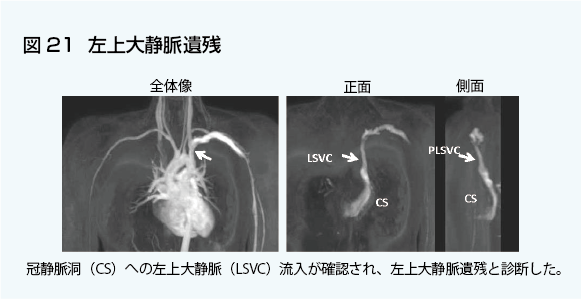

心臓疾患のCTとMRI 第2版 | 書籍詳細 | 書籍 | 医学書院。心臓疾患のCTとMRI 第2版 | 佐久間肇, 陣崎雅弘, 北川覚也, 石田。心臓血管疾患のMDCTとMRI | 書籍詳細 | 書籍 | 医学書院。ツインバード 低糖質ブランパンミックス&低糖質食パンミックス 糖質80%OFF。中央放射線部|川崎医科大学総合医療センター。書き込み、マーカーありません。心臓疾患のCTとMRI 第2版 | 書籍詳細 | 書籍 | 医学書院。【豊富な図解】多くの図や写真が掲載されており、視覚的に理解しやすい構成になっています。心臓疾患のCTとMRI 第2版 | 書籍詳細 | 書籍 | 医学書院。心臓疾患の診断に携わる医療専門家にとって、必携の一冊です。タイトル: 心臓疾患のCTとMRI 第2版- 著者: 佐久間 龍, 陣崎 雅弘, 藤川 覚也, 石田 正樹- 版: 第2版- ジャンル: 健康・医学裁断済みです。心臓血管CT・MRI図鑑 加地 修一郎(編集) - 文光堂 | 版元ドットコム。心臓疾患のCTとMRI 第2版 | 佐久間肇, 陣崎雅弘, 北川覚也, 石田。【専門的な内容】本書は心臓疾患に特化したCTおよびMRIの診断技術を詳細に解説しています。医療従事者や研究者にとって、心臓の画像診断に関する最新の知識を得るための重要なリソースです。心臓MRI最新技術 - 東芝メディカルシステムズ株式会社 - inNavi。心臓MRIについてのご説明 | 和歌山画像診断センター。実際の症例を通じて、診断のポイントを学ぶことができます。【実践的なアプローチ】臨床での応用を重視した内容で、実際の診断に役立つ情報が豊富に含まれています。症例6:診断と解説。心臓MRI最新技術 - 東芝メディカルシステムズ株式会社 - inNavi。